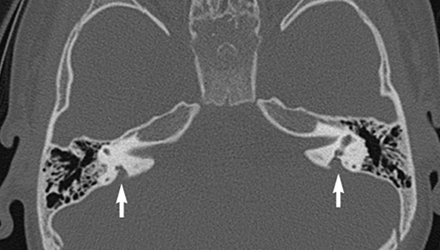

SLC26A4基因定位于人類染色體7q31,SLC26A4基因和大前庭導(dǎo)水管綜合征相關(guān)突變位點(diǎn)的發(fā)現(xiàn),證實(shí)SLC26A4是大前庭導(dǎo)水管綜合征的責(zé)任基因。

我們平時(shí)提到的“一巴掌打聾”、“一跤摔聾”其實(shí)都與SLC26A4基因突變有關(guān),絕大多數(shù)大前庭導(dǎo)水管綜合征都是SLC26A4基因突變?nèi)堑牡湣?/p>

SLC26A4基因編碼一種叫“Pendrin”的跨膜轉(zhuǎn)運(yùn)蛋白,在機(jī)體離子成分平衡的維持中發(fā)揮重要作用。

在內(nèi)耳,Pendrin表達(dá)于內(nèi)淋巴管、內(nèi)淋巴囊、橢圓囊、球囊等處,異變的蛋白將對(duì)這些結(jié)構(gòu)的正常生理功能產(chǎn)生影響,引發(fā)聽損。

SLC26A4基因突變導(dǎo)致的大前庭導(dǎo)水管綜合征的典型表現(xiàn)為兒童時(shí)期的聽力損失,90%的患者為雙側(cè)性,聽力損失程度不一,可表現(xiàn)為接近正常或重-極重度。

病程可為穩(wěn)定性、進(jìn)行性或波動(dòng)性,聽力可逐步下降至全聾;跌倒、撞擊等行為或無外界影響都可能引發(fā)聽力的下降。